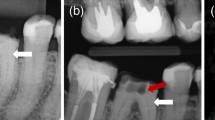

A 24-year-old woman was referred from a private dental clinic to the dental hospital due to recurrent swelling and pain in the vestibular region of teeth 23-25 despite receiving endodontic treatment over the past two weeks. Medical and family history were noncontributory. The extraoral examination showed no apparent abnormalities. The intraoral examination revealed temporary sealing materials on the occlusal surface of teeth 24 and 25 (Fig. 1B, green arrow). Compared with the contralateral canine, tooth 23 exhibited a larger mesiodistal diameter (Fig. 1A) and had a small pit on the mesial part of the palatal surface of tooth 23 (Fig. 1B, black arrow). For teeth 23-25, there was no evidence of caries, restorations, increased tooth mobility, or increased probing depth. Pulp sensibility tests indicated no response to cold/hot or electric pulp tests. Some discomfort was experienced on direct vertical percussion, and slight pain was felt upon palpation of the periapical area. The buccal/labial alveolar mucosa related to teeth 23-25 was normal, with no swelling or sinus tract (Fig. 1C). The periapical radiograph (Fig. 1D) revealed Oehlers’ Type II CDI in tooth 23 and a radiolucent lesion in the periapical region of teeth 23-25. To elucidate the morphology of tooth 23 and the extent of the periapical radiolucency [15, 16], a CBCT scan (Morita, Kyoto, Japan) was taken with a voxel size of 125 μm and exposure parameters of 90 kV, 5.0 mA and 17.5 s with the patient's consent. The CBCT scan revealed the following findings: 1) The upper half of the invagination was tooth-shaped and highly compressed the true root canal into a crescent shape, while the lower half was irregularly cylindrical and compressed the root canal into a ring. 2) The periapical radiolucency extended from the mesial side of tooth 23 to the distal side of tooth 25 and involved the buccal wall of the alveolar bone but was not connected to the maxillary sinus. 3) A lateral perforation was observed on the mesial wall of the pulp cavity of tooth 24 (Fig. 1E-G). Three-dimensional reconstruction images of the complex canal morphology of tooth 23 using Mimics 19.0 (Materialise, Belgium) were shown in Figure 2A-B.

Preoperative examination of case 1. A Tooth 23 exhibited a larger mesiodistal diameter than tooth 13. B Green arrow: temporary sealing material on the occlusal surface of teeth 24 and 25; black arrow: a small foramen caecum on the mesial part of the palatal surface of tooth 23. C No swelling or sinus tract was observed at the buccal/labial alveolar mucosa related to teeth 23-25. D The periapical radiograph revealed CDI in tooth 23 and a radiolucent lesion in the periapical region of teeth 23-25. E-G CBCT scan images: E Axial slices at various points denoted on the sagittal section. The upper half of the invagination appeared tooth-shaped, compressing the true root canal into a crescent, while the lower half showed an irregularly cylindrical shape, compressing the true root canal into a ring. F The periapical radiolucency extended from the mesial side of tooth 23 to the distal side of tooth 25. G A lateral perforation on the mesial wall of tooth 24

A 39-year-old woman was referred to the hospital due to pain in the left upper anterior tooth after crown preparation to correct tooth discoloration. Medical and family history were non-contributory. The extraoral examination revealed no apparent abnormalities, and the intraoral examination revealed crown preparation of tooth 22, along with an access cavity in the middle of its palatal surface (Fig. 4A, B, white arrow). There was no tooth mobility or increased probing depth. Pulp sensibility tests indicated no response to cold/hot or electric pulp tests. The tooth exhibited intense discomfort on direct vertical percussion and pain upon palpation of the periapical area. Radiographic examination revealed Oehlers’ Type II CDI in tooth 22. The upper half of the invagination was tooth-shaped and highly compressed the true root canal into a ring, while the lower half was irregularly cylindrical and compressed the root canal into a crescent shape. The periodontal ligament space was widened (Fig. 4C, D). Three-dimensional reconstruction images depicted the complex canal morphology of tooth 22 (Fig. 4E). The diagnosis was Type II CDI with acute apical periodontitis. Four debridement routes were designed, and corresponding templates were fabricated (Fig. 4F, G). GE-based RCT was implemented using the same procedure as described in case 1 (bur: TF-11, MANI, Utsunomiya, Japan; Fig. 4H-K). The three-year follow-up showed no obvious abnormalities, and the treated tooth was asymptomatic (Fig. 4L, M and Fig. S2).

Treatment process and follow-up of Case 2. A, B Preoperative intraoral examination. C, D Preoperative periapical radiograph and CBCT scans. E Three-dimensional reconstruction of tooth 22 and virtual simulation of four debridement routes designed based on the MICRO principle. F, G Procedure for fabricating the templates. H, I Four opening access cavities guided by templates. J, K After root canal filling, the effect was verified. L, M 3-year follow-up